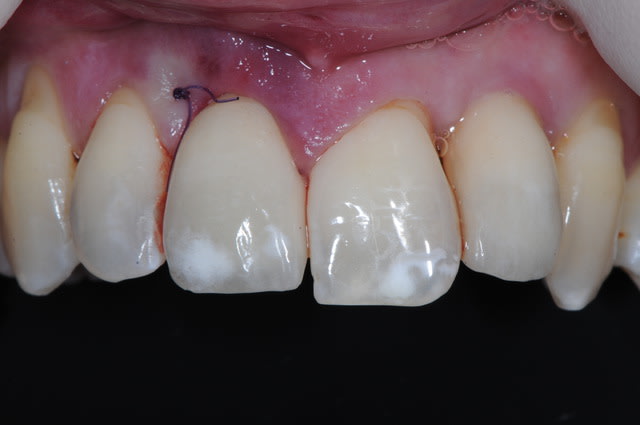

Je poste le cas en avant premiere ici.

C'est tout frais du mois dernier.

Dsc 0964 qivimn - Eugenol

Bourdon scan avant qxy44n - Eugenol

Dsc 0936 e8bl2k - Eugenol

Dsc 0945 thnkyf - Eugenol

Dsc 0947 iegdot - Eugenol

Dsc 0952 h6fydk - Eugenol

Dsc 0953 oxlmkb - Eugenol

Dsc 0954 fcxmez - Eugenol

Dsc 0955 bz9tga - Eugenol

Dsc 0967 dr54to - Eugenol

Bourdon 3d smbqqr - Eugenol

Bourdon scan apres xgacpr - Eugenol

La photo #4 montre l'implant en position finale ?

Oui, l'implant est en position finale sur la photo 4.